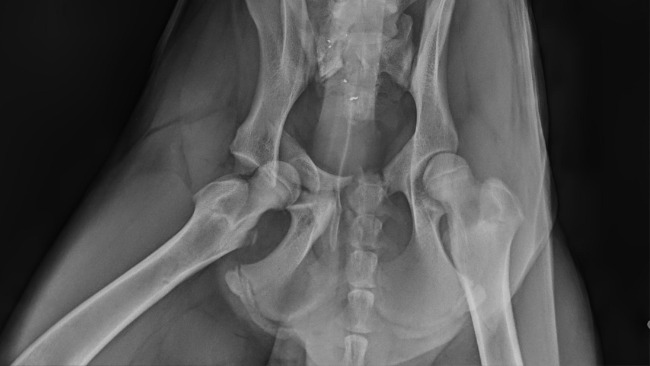

16 stycznia otrzymaliśmy zgłoszenie o potrąconym owczarku niemieckim leżącym na drodze w jednej z okolicznych wsi. Sprawca potrącenia odjechał z miejsca wypadku nie udzielając zwierzęciu pomocy. Dopiero inny kierowca, zauważywszy psa, zatrzymał się i zadzwonił do nas. Ruszyliśmy natychmiast nie wiedząc, w jakim stanie jest pies, ile bólu już zniósł i czy zdążymy na czas. Na miejscu naszym oczom ukazał się, leżący na poboczu drogi, piękny, młody psiak. Jamal cierpiał w milczeniu, ale wykonane w lecznicy zdjęcie RTG nie pozostawiło złudzeń — złamana kość biodrowa, kość łonowa, a do tego poważne uszkodzenie ogona.